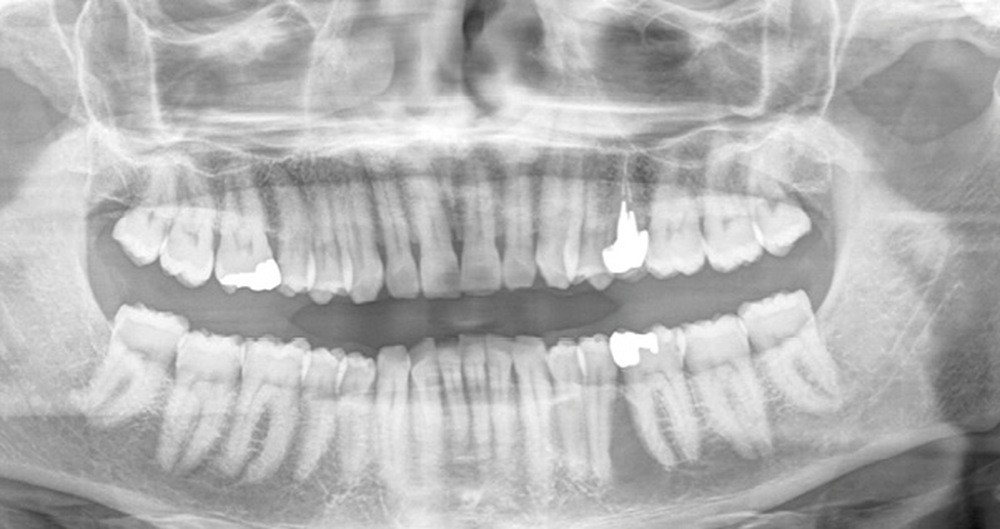

L’exploration chirurgicale de la lésion a été réalisée sous anesthésie locorégionale permettant de mettre en évidence, après ostectomie, une lésion kystique s’étendant sur les faces linguale et vestibulaire de 35 impliquant l’avulsion de cette dent. L’énucléation de la lésion, à distance du pédicule vasculo-nerveux alvéolaire inférieur, a été réalisée.

L’examen anatomopathologique a conclu à un kératokyste.

Le risque de récidive étant important, le patient a été prévenu de la nécessité de pratiquer un contrôle radiographique annuel par orthopantogramme (OPT), éventuellement complété par tomodensitométrie (TDM) ou tomographie volumétrique (cone beam CBCT).

L’ossification de la perte de substance osseuse est obtenue en 6 semaines mais ne sera visible sur les clichés radiographiques de contrôle que dans un délai de 6 à 9 mois.

Les kératokystes peuvent survenir à tout âge. Ils se manifestent par une voussure osseuse vestibulaire qui peut être douloureuse.

Radiologiquement, la lésion apparaît comme une clarté uni- ou multiloculaire bien limitée. Le diagnostic différentiel peut être posé avec l’améloblastome ; c’est la chirurgie qui permettra le traitement et la conclusion anatomopathologique.